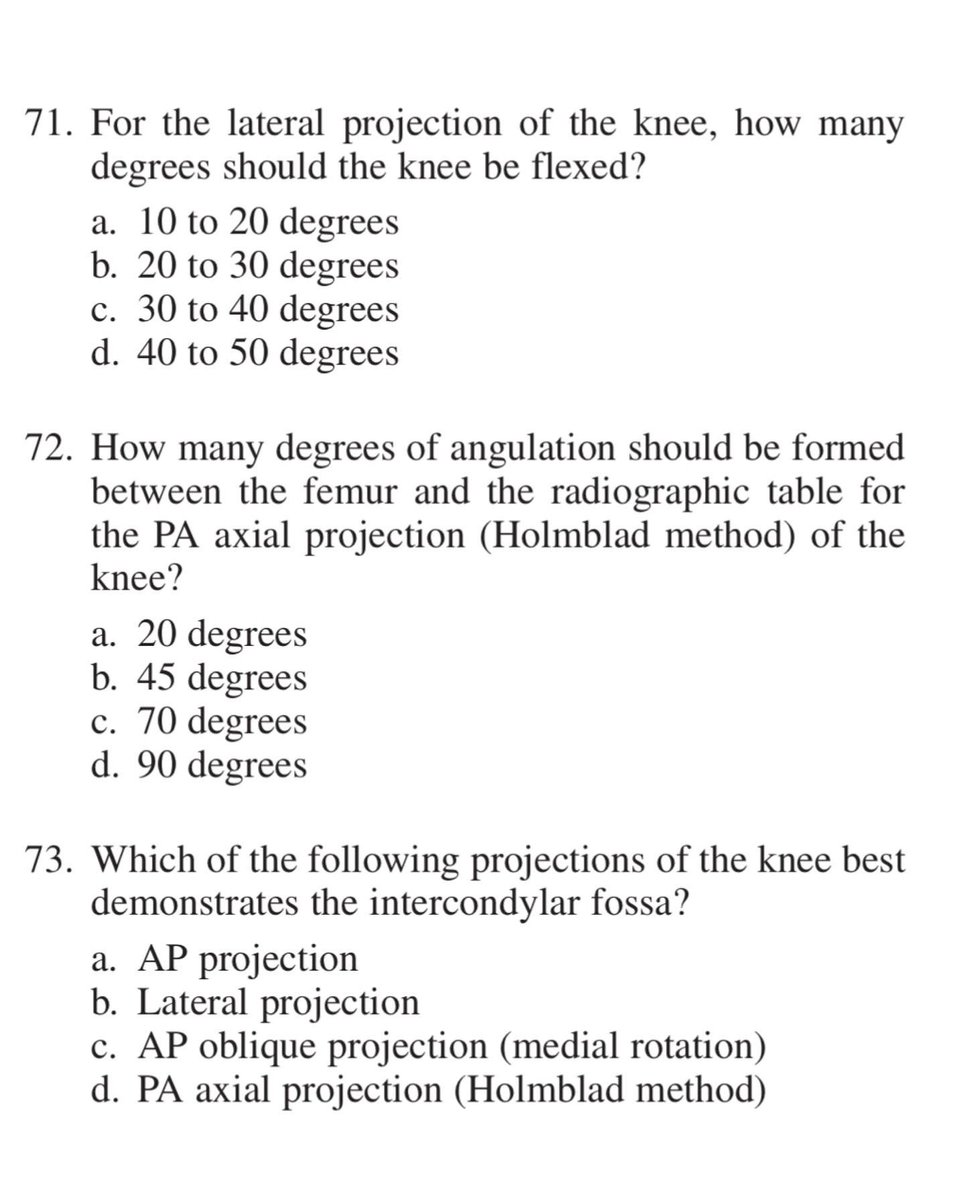

#radiology #radiography #xray #radiographer #radtech #srtle

من الاسئلة الاكثر أهمية في تصوير الركبة بالأشعة السينية فلنتشارك في الحل

SELF-TEST:

POSITIONING OF THE LOWER LIMB

Answer the following questions by selecting the best choice.

Reference (Merrill’s Atlas 12 edition)